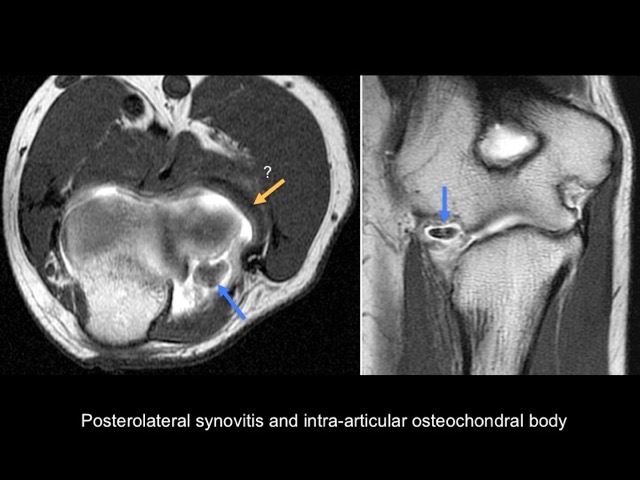

32 year-old-man with posterolateral pain, instability and snapping elbow

Posterolateral elbow instability with intra-articular annular ligament luxation. Associated focal posterolateral synovitis and intra-articular loose body. Reference article.

annular ligament of radius ( RID2048 )